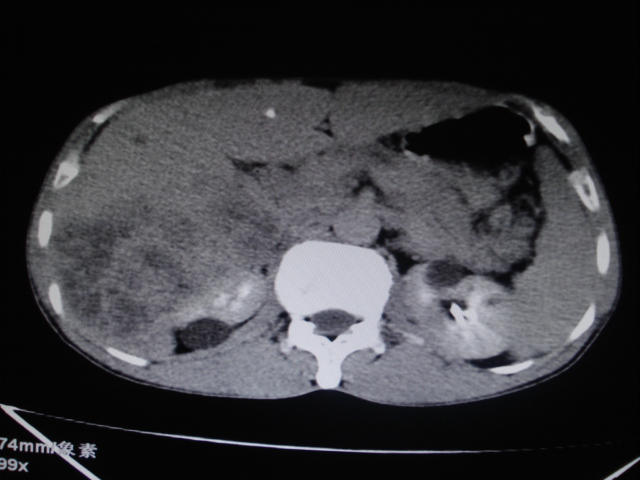

标题: CT24041:肝脏占位,请会诊!

男性,62岁。肝右叶占位,平扫及增强如下,延迟期为15分钟扫描。

给病史及实验室检查!多考虑胆管细胞癌;右肾囊肿。

1)不均匀性脂肪肝。2)肝硬化。3)肝右叶肝癌不排除。4)右肾囊肿。